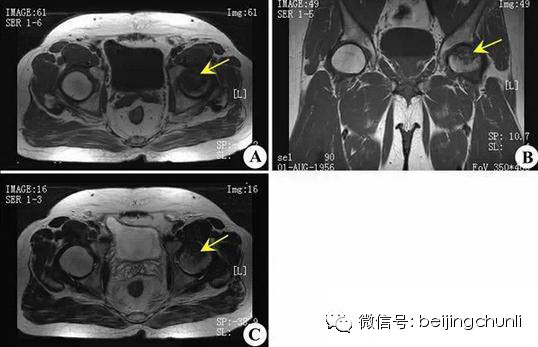

Ⅲ期股骨头变形,软骨下骨折、塌陷、新月体形成。T1加权呈带状低信号,T2加权示中等或高信号,为关节积液进入软骨下骨折线的裂隙。新月形坏死骨发生应力性软骨下骨折、塌陷并与关节软骨分离。由于纤维组织长入形成致密的无血管墙,使修复被阻挡,进入坏死骨的修复受限。

股骨头坏死

上图为Ⅲ期